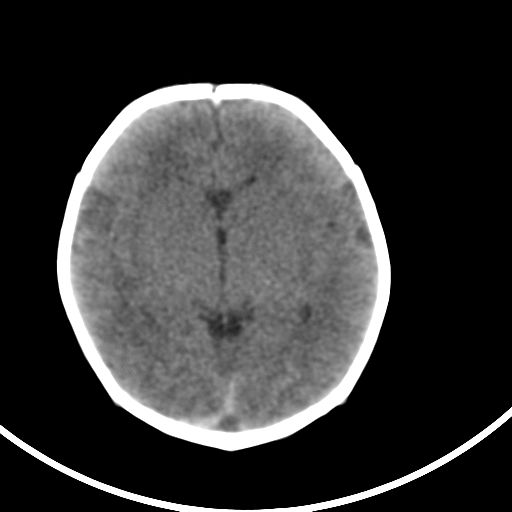

新生儿3天,超过预产期5天剖宫产,有缺氧病史,具体评分不详,现反应差,肌张力低,前囟平,原始反射存在,无苦闹等。

kaolv小脑幕,后纵裂区蛛网膜下腔出血;轻度脑肿胀

矢状窦旁征——支持蛛网膜下腔出血